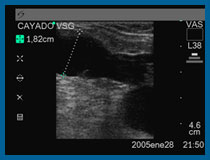

A nivel vascular, el Eco-Doppler color se utiliza, para “ver” en directo, con el Eco los vasos sanguíneos, su calibre, su estructura, y las modificaciones en sus paredes.

Con el Doppler y Doppler Color, medimos la velocidad de flujo, e indirectamente el volumen circulante en un determinado vaso ( arteria o vena) .

A nivel de venas varicosas, nos permite hacer un “mapeo” de todas ellas a lo largo de la extremidad, observando la disposición superficial o profunda y permitiendo localizar los puntos de reflujo desde el sistema venoso superficial al profundo.

A nivel de arterias, podemos estudiar especialmente las consecuencias de la arterioesclerosis, u otras enfermedades arteriales, observando la deformación de las paredes arteriales, la presencia de placas ateromatosas, y midiendo el flujo o volumen de sangre circulante de una determinada arteria a un determinado nivel. Se estudian especialmente los llamados troncos supraórticos (arterias carótidas, subclavias y vertebrales) y las arterias de las extremidades superiores o inferiores. Igualmente la aorta torácica y abdominal arterias ilíacas, arterias renales etc.